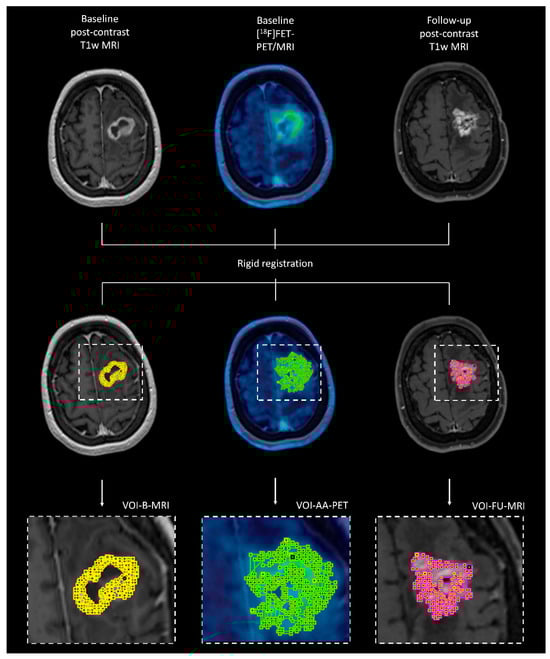

2.4. Co-Registration of Different Imaging Modalities at Different Time Points